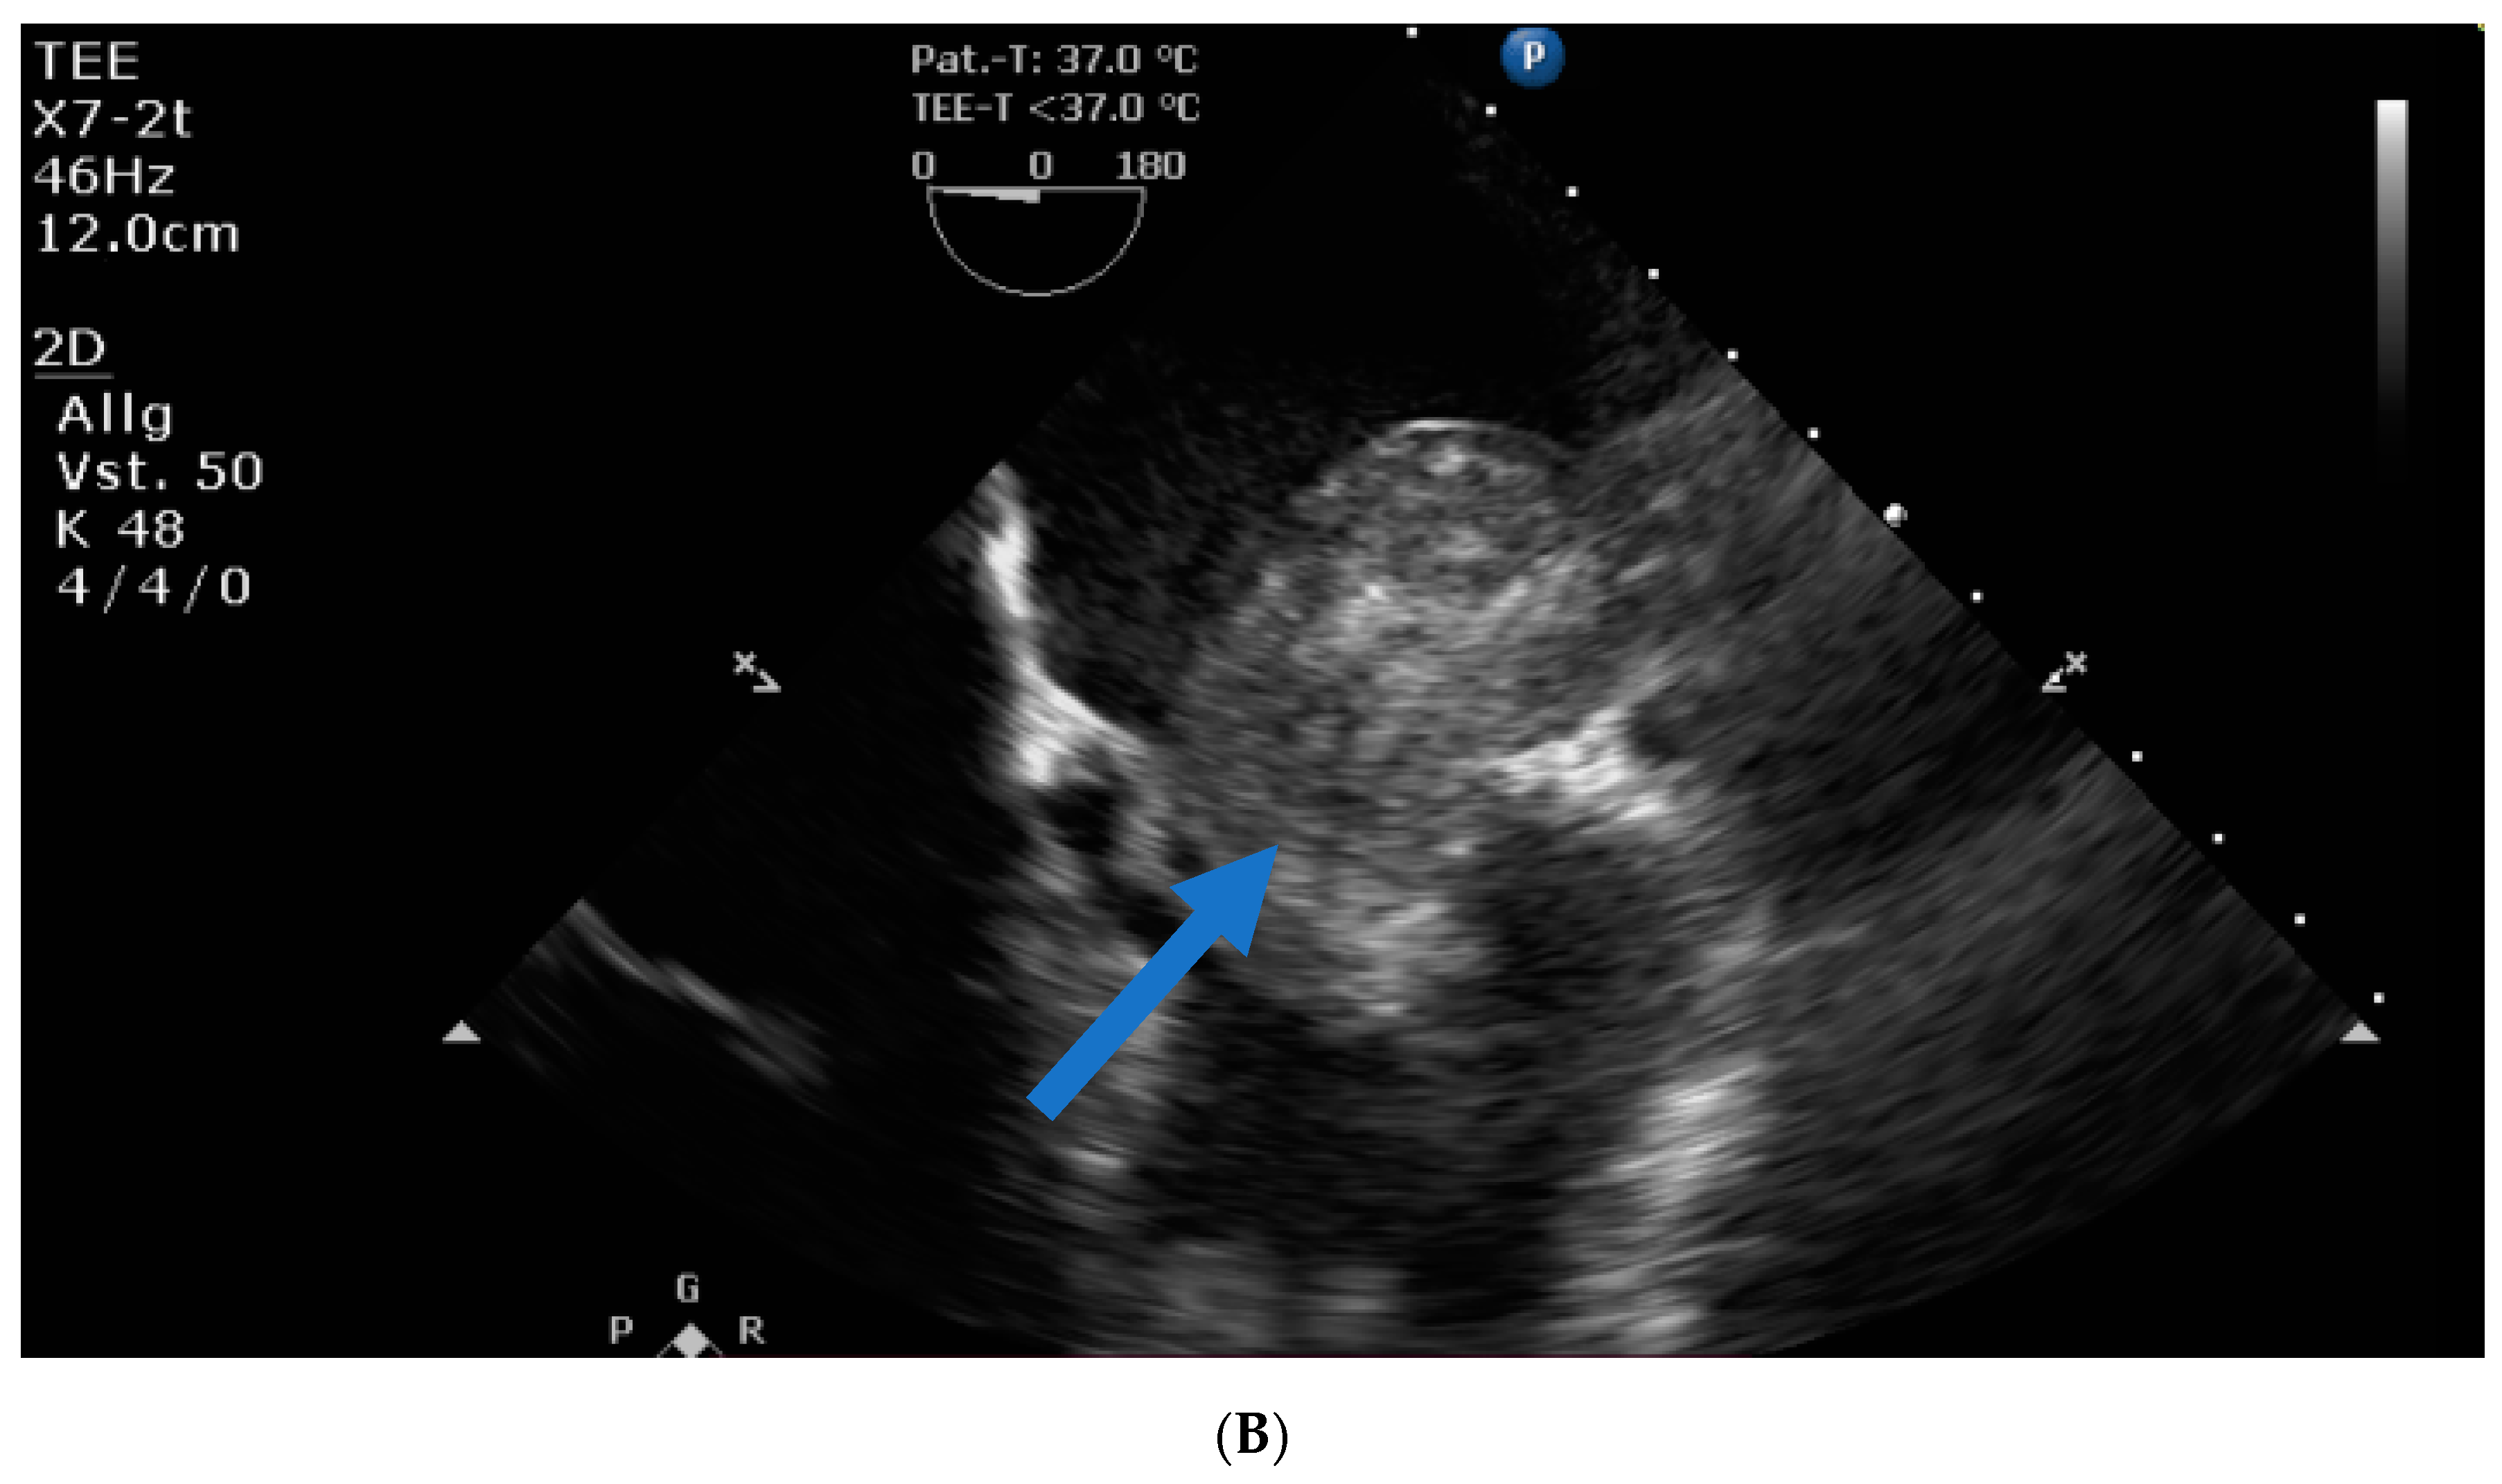

Transthoracic and transesophageal echocardiography revealed a large mass (40 × 60 × 24 mm) in the left atrial lateral wall, extending to the mitral valve (Figure 1A,B). Both atria were severely dilatated. The left ventricle was normal in size with an ejection fraction of 55%, an apicolateral/midlateral hypokinesia and a mild diastolic dysfunction. The normal-sized right ventricle had impaired systolic function. A hemodynamically irrelevant pericardial effusion was present.

The following day, the patient acutely decompensated and developed catecholamine-dependent cardiogenic shock. The emergency echo showed almost complete obstruction of the mitral valve inflow by the huge mass. Laboratory analysis revealed lactic acidosis and a further drop of thrombocytes to 23 × 103/µL.

Figure 1. (A) Huge left atrial mass (arrow indicates cardiac mass). (B) Huge left atrial mass prolapsing into the mitral valve in diastole and thus obstructing the inflow of the left ventricle (arrow indicates cardiac mass).